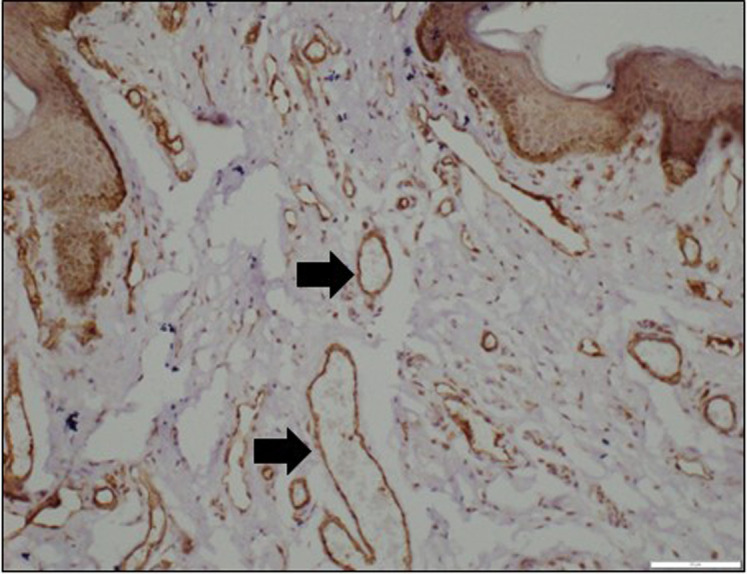

目的:包皮皮瓣在尿道下裂修复中应用广泛,但包皮组织的愈合潜力仍然是一个值得关注的问题。本研究旨在评估尿道下裂患者包皮与对照组相比的微血管密度(MVD)和生长因子受体(VEGFR和TGF-!R)水平,并比较包皮内外层的这些参数,以确定其在尿道下裂修复中的相对适宜性。方法:该研究包括14岁以下接受原发性尿道下裂手术的儿童和接受选择性包皮环切术的个体作为对照。取内包皮和外包皮标本,用CD31抗体进行免疫组化染色,评估MVD、VEGFR和TGF-!R抗体评估生长因子水平。用组织学评分系统半定量分析染色强度。结果:内包皮微血管密度显著高于外包皮(P < 0.05),提示内包皮组织在尿道下裂修复中具有潜在优势。相反,在病例中,外包皮的VEGFR水平显著高于外包皮(P < 0.05),表明这两层之间的愈合潜力不同。转化生长因子!对照组内包皮和外包皮的受体水平均显著低于对照组(P < 0.05)。其他研究结果均无统计学意义。结论:内包皮较高的MVD可能是尿道下裂修复的首选方法。然而,内包皮和外包皮之间VEGFR水平的差异突出了复杂的愈合动力学,强调需要进一步研究以得出明确的结论。

Objective: Preputial flaps are frequently used in hypospadias repair, but the healing potential of preputial tissue remains a concern. This study aimed to evaluate the microvessel density (MVD) and growth factor receptor levels (VEGFR and TGF-!R) in the prepuce of patients with hypospadias compared to controls and to compare these parameters between the inner and outer preputial layers to determine their relative suitability for hypospadias repair. Methods: The study included children under 14 years of age undergoing primary distal hypospadias surgery as cases and individuals undergoing elective circumcision as controls. Specimens from the inner and outer prepuce were collected, and immunohistochemical staining was performed using CD31 antibodies to assess MVD and VEGFR and TGF-!R antibodies to evaluate growth factor levels. The staining intensity was semi- quantitatively analyzed using a histological scoring system. Results: Microvessel density was significantly higher in the inner prepuce than the outer prepuce in both cases and controls (P < .05), suggesting a potential advantage of inner prepuce tissue in hypospadias repair. Conversely, VEGFR levels were significantly higher in the outer prepuce in cases (P < .05), indicating different healing potentials between these layers. Transforming growth factor ! receptor levels were significantly lower in both the inner and outer prepuce of controls compared to cases (P < .05). Other findings did not reach statistical significance. Conclusion: The higher MVD in the inner prepuce suggests it may be preferable for hypospadias repair. However, the differential VEGFR levels between the inner and outer prepuce highlight complex healing dynamics, emphasizing the need for further research to draw definitive conclusions.